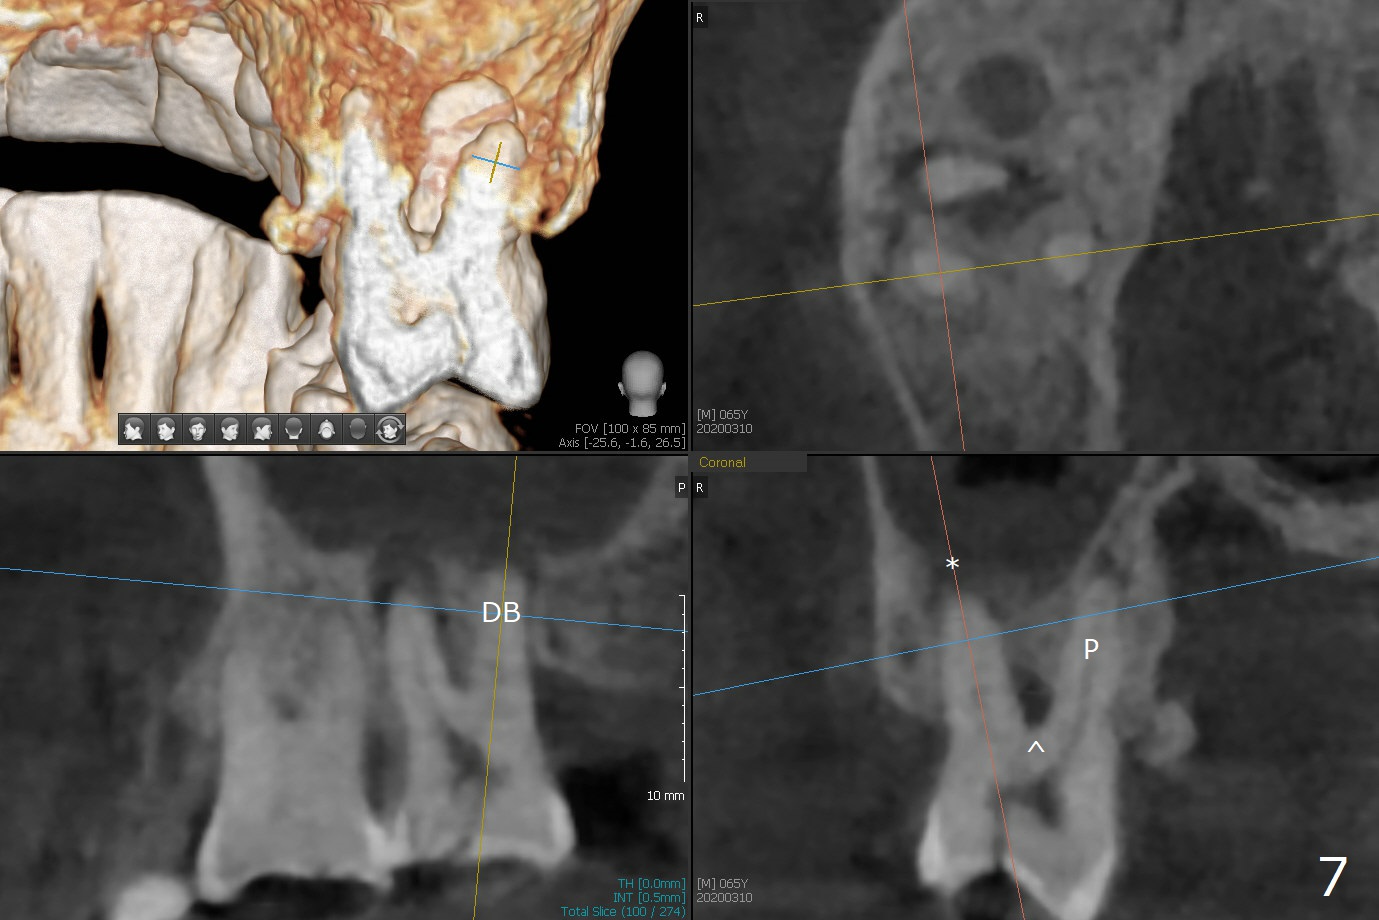

After implant placement at #13 six months post bone graft (Fig.1), reexami-nation shows that the tooth #2 cracks (Fig.2-4). The bony defect area is easier to identify with CT (between MB and P roots of #2) than without CT (M) for #13. There is no bone height reduction after extraction of #15 (Fig.5). Due to new coronal virus outbreak, the patient wants extraction first. The sinus floor perforates (*) apical to MB (Fig.6) and DB (Fig.7) roots. After debridement, sinus lift will be conducted using allograft hydrated with GEM21S liquid portion. The same mix will be used for socket preservation. With high concentration of growth factor, it is hoped that bone density in the sockets will increase quick and high enough for future implant, as compared to #13 of the same patient.